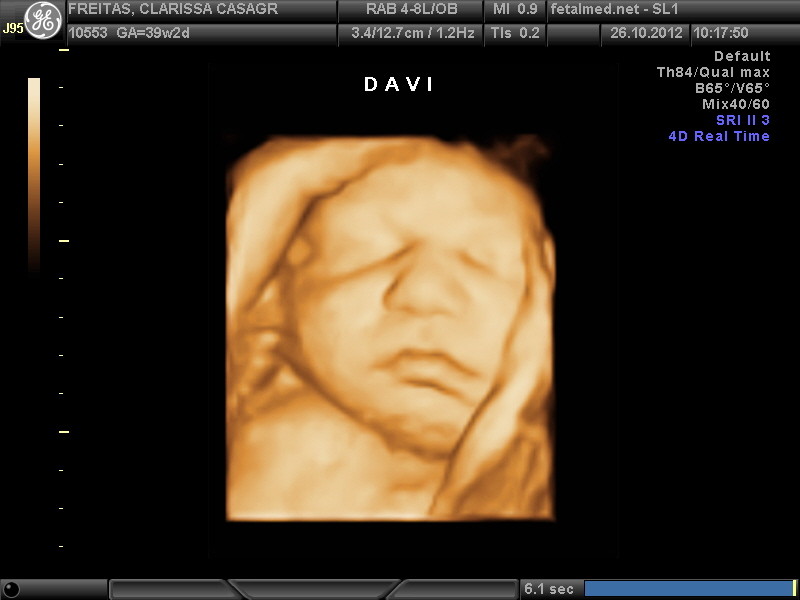

O Bebê

A maior parte do vérnix (ou lanugo) já desapareceu e o bebê se prepara para nascer em poucos dias. O crânio ainda não é totalmente sólido, apresentando-se mais amolecido nas 5 fontanelas (também conhecidas por moleiras), que ainda estão separadas e podem ser apertadas umas contra as outras. Assim o parto pode alongar e moldar a cabeça fetal, uma precaução de segurança para reduzir o diâmetro do crânio, permitindo uma expulsão mais fácil da cabeça, durante a passagem do feto pelo canal de parto, sem provocar danos ao cérebro. Após o parto, a cabeça do bebê retorna a sua forma arredondada.